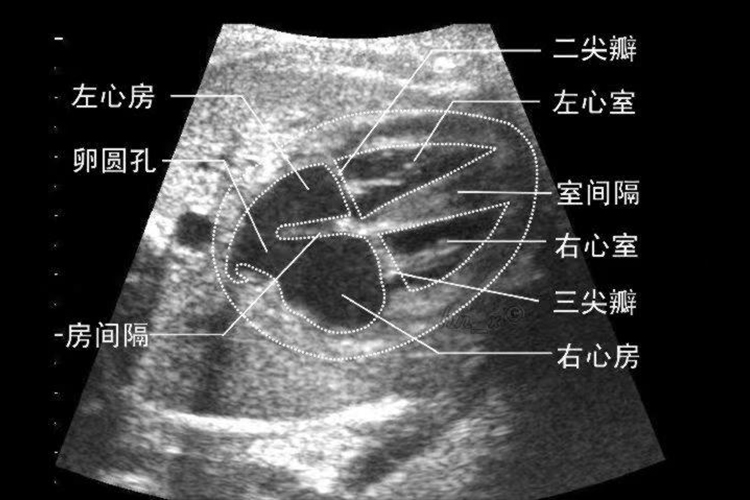

- 评估心脏结构:心脏超声检查可以详细显示心脏的内部结构,包括心房、心室、心脏瓣膜以及大血管的连接等。通过测量和分析这些结构,可以对心脏的形态、大小和功能进行全面评估。